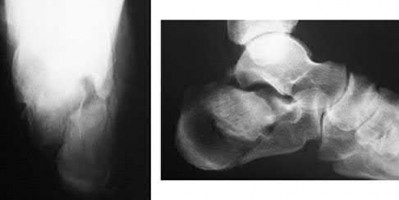

A 34-year-old male sustains the closed injury seen in Figure A as a result of a high-speed motor vehicle collision. What is the most appropriate next step in treatment?

The radiograph shows a comminuted pilon fracture, which is associated with high-energy trauma and significant soft tissue injury. The tested concept here is the importance of avoiding definitive reduction and fixation of this high-energy injury, which has been shown to be associated with an increased risk of wound complications and deep infections (as compared to staged treatment with usage of a spanning external fixator).

Patterson et al. reviewed 23 consecutive patients with comminuted distal tibia fractures. They showed 0% infections or wound-healing problems in their patient population treated with a two-staged protocol. Their protocol involved fibula fixation with an intramedullary implant and application of a medial external fixator to to regain length and restore anatomic alignment. Reevaluation of the limb occurred ten to fourteen days later for definitive fixation.

Sirkin et al. retrospectively reviewed 40 closed and 17 open pilon fractures (AO types 43A-C) that were treated with staged surgical management (avg. time from ext. fix. to formal reconstruction was 14 days (range 4 to 31) They reported 17% post-operative wound complication in the closed group and 11% post-operative wound complication in the open group (Gustilo Type I-III). They suggest the technique was successful in both closed and open pilon fractures.